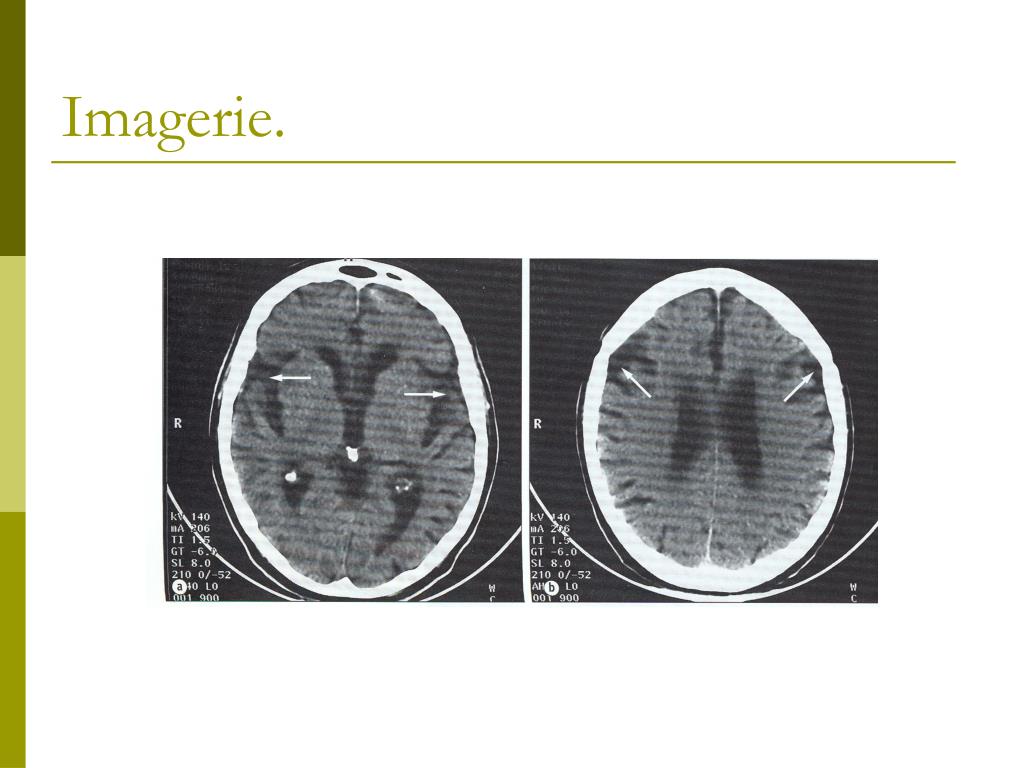

4. Histoire clinique. • Affection actuelle : • Patiente retrouvée par l’infirmière à son domicile avec des plaintes de dyspnée. • À l’admission : • Dyspnée. • Cyanose. • Désorientation spatio-temporelle. • Notion de détérioration cognitive progressive depuis 1 an avec d’abord des pertes de mémoire puis des difficultés à reconnaître des choses, les gens sans empêcher la patiente de rester seule à domicile. • Scan cérébral : atrophie corticale importante avec présence de lacunes sous-corticales.

19. Imagerie.

20. Macroscopie. • Atrophie sévère diffuse du cortex cérébral et de l’hippocampe avec secondairement un élargissement du système ventriculaire.